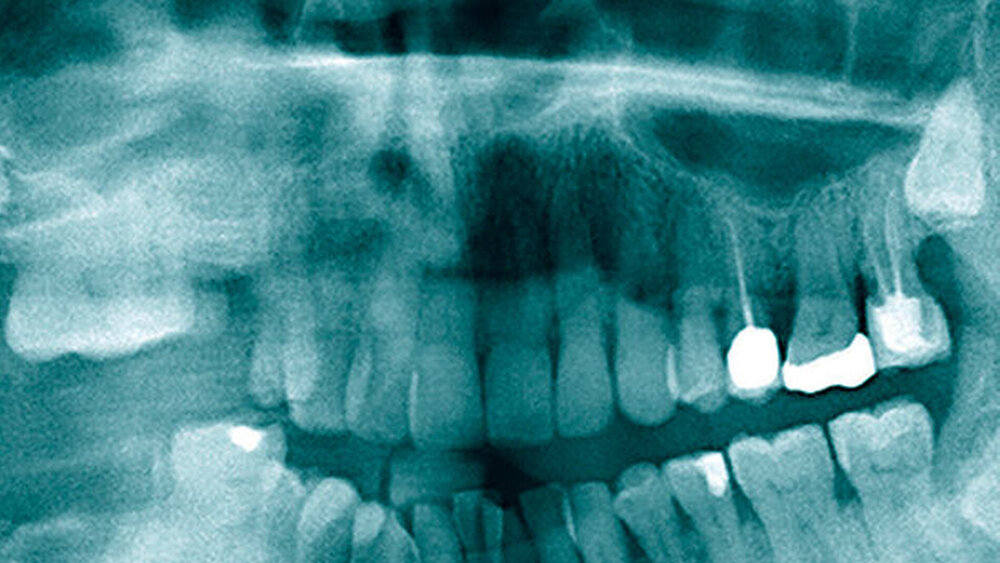

Ein 75-jähriger Patient stellte sich mit Verdacht auf einen perimandibulären Abszess in der Klinik vor. Ursächlich war ein retinierter Zahn 48, bei der Aufnahme lagen Schluckbeschwerden und eine perimandibuläre Schwellung vor. Der Abszess wurde notfallmäßig drainiert und es kam zum Ablauf von Pus (Abbildung 1), eine kalkulierte Antibiose mit Aminopenicillin/Clavulansäure wurde eingeleitet.